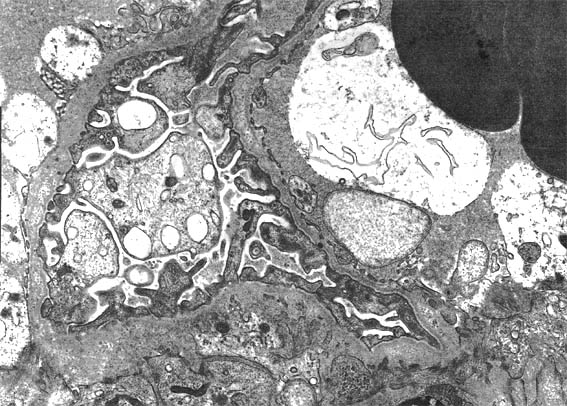

Figura 7.

Imagen de microscopía electrónica, X6.000.